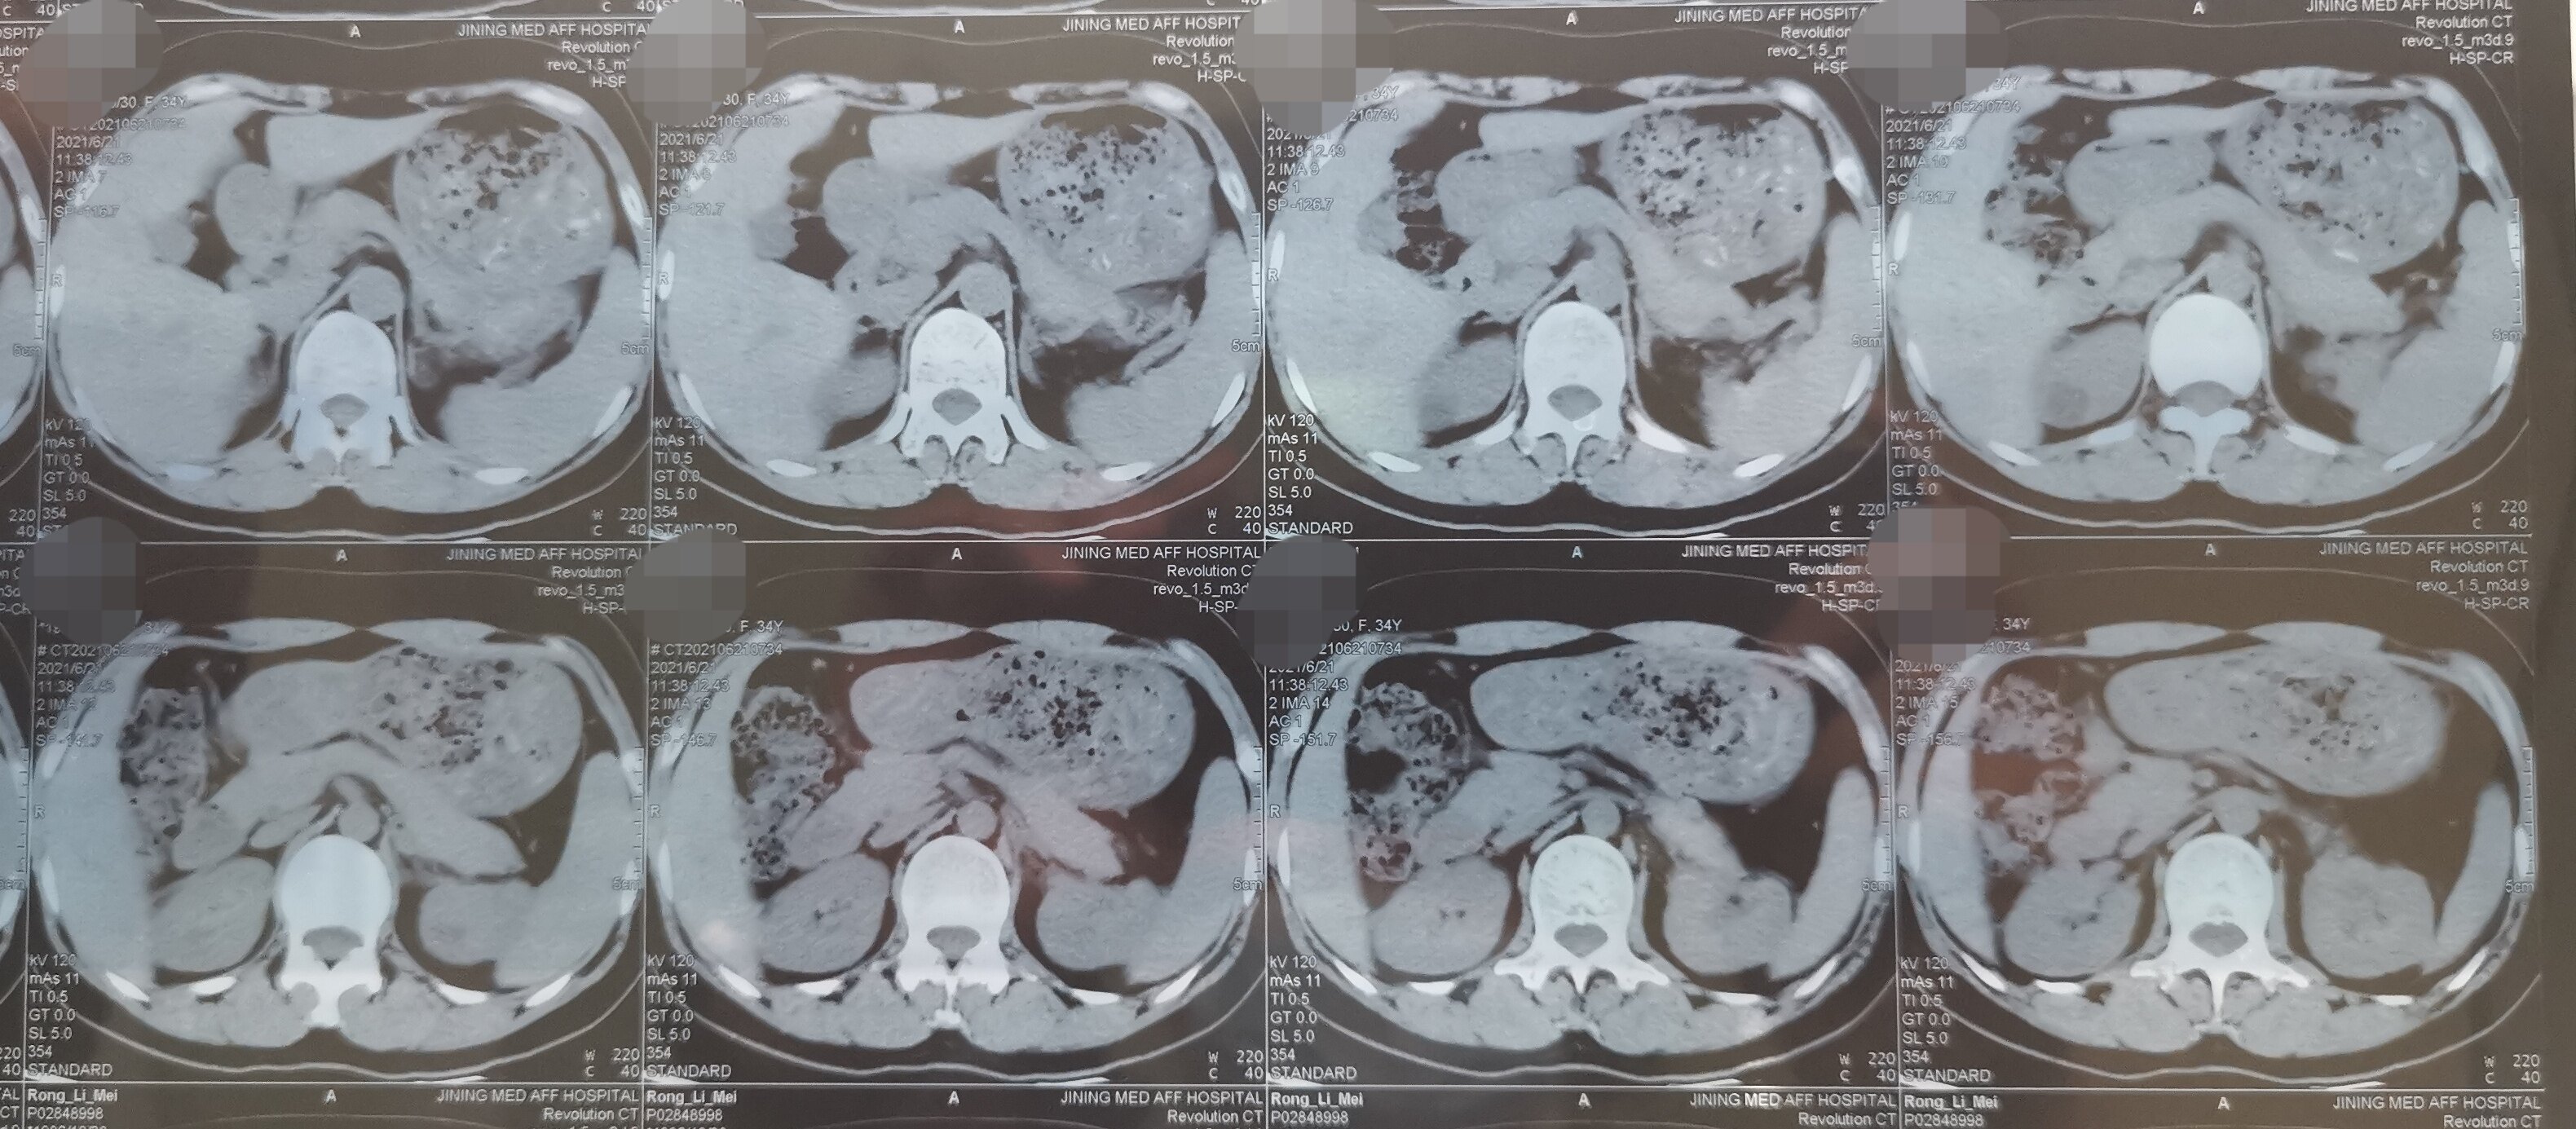

【病例讨论】女,52岁,多囊肝伴双肾"壮观"多囊肾 [病例帖]